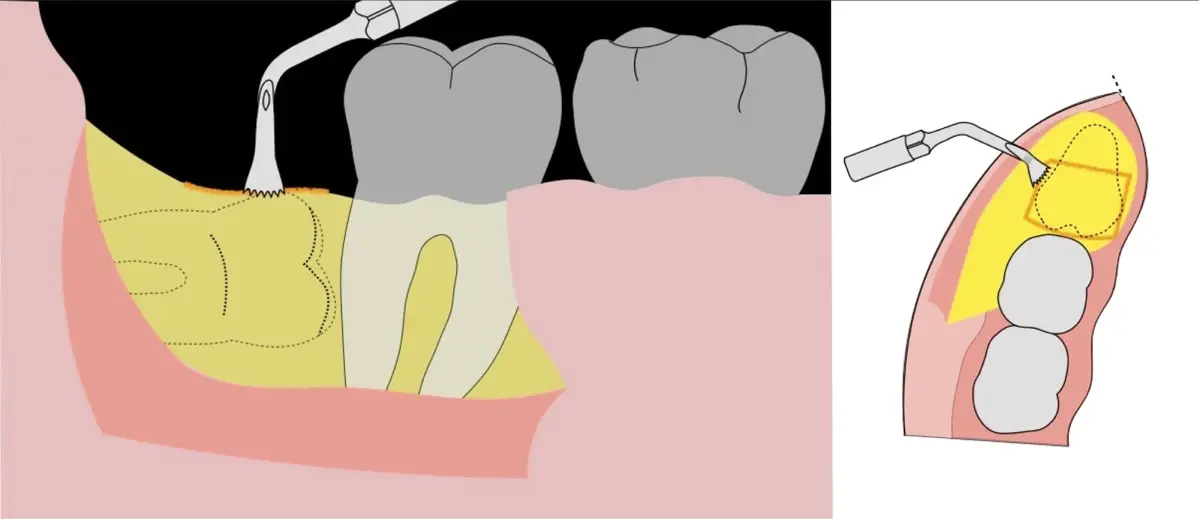

En contraste, el instrumento piezoeléctrico utiliza un corte micrométrico que retira un área de superficie mínima de hueso, y reduce el riesgo de termonecrosis marginal en comparación con las fresas rotatorias convencionales.9 Los micromovimientos mejoran la precisión en el corte y el control táctil, y eliminan las macrovibraciones que se producen con los instrumentos rotatorios.10 Su frecuencia de oscilación es la amplitud de 60-200 μm horizontalmente y de 20-60 μm en sentido vertical, lo que es muy inferior en comparación con las micro sierras oscilantes; por lo tanto, proporciona cortes de osteotomía precisos y seguros. Adicionalmente, posee vibraciones ultrasónicas que descomponen el líquido de irrigación en partículas muy pequeñas (fenómeno de cavitación, que produce un efecto hemostático y así reduce la pérdida de sangre), lo que proporciona una visión clara y sin obstáculos del campo quirúrgico11,12.

Es imprescindible conocer la ubicación de la tercera molar. Se puede emplear, adicionalmente a la evaluación clínica, herramientas radiográficas (panorámica y periapical) y tomográficas (Cone beam) para determinar la posición, grado de retención y proximidad a estructuras vecinas de riesgo como el nervio dentario inferior y así evitar lesiones (Figura 1).

El procedimiento se inicia colocando anestesia troncular para bloqueo del nervio dentario inferior y sus ramas. Luego, se establecerá el diseño de acceso según la disposición de la molar a extraer. Para fines didácticos, se explicará cómo se realizaría la extracción de la molar de la Figura 1: se realiza una incisión horizontal a nivel de la zona retromolar hasta llegar a distal de la segunda molar, continuándose con una incisión intrasurcular hasta mesial de la segunda molar, finalizando con una incisión vertical a espesor total hasta llegar a la línea mucogingival (Figura 2).